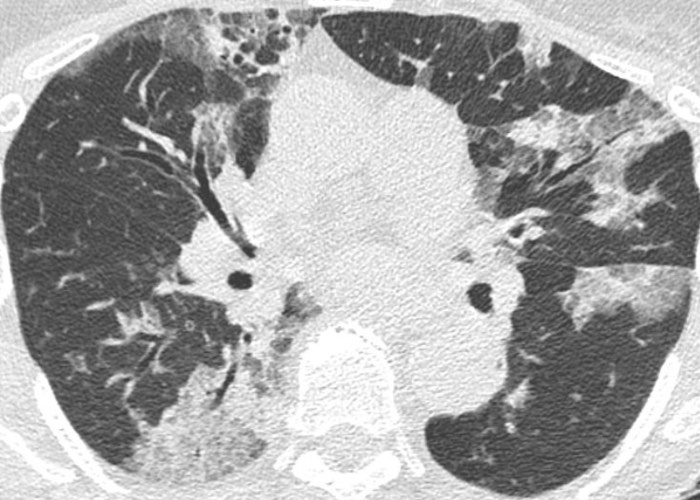

- abcès = bactéries anaérobies dans l'inhalation, staph, pyo, klebsiella

- pneumonie nécrosante /!\ faux-anévrysmes = staph, BK, fongique